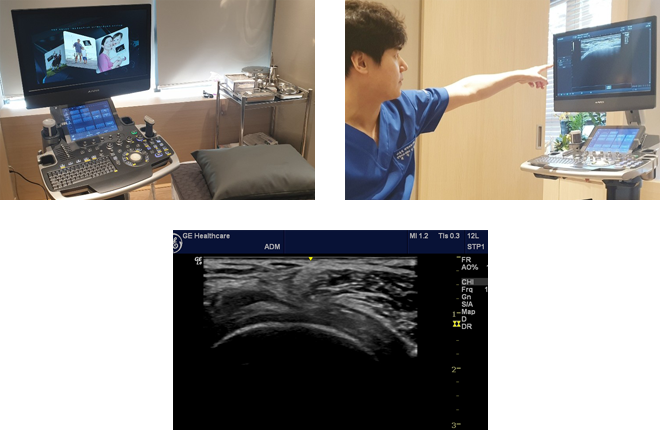

대치역삼바른길정형외과의원에서는 안전하고 정확한 시술을 위해

정확도가 뛰어난 정밀진단 장비를 사용하고 있습니다.

인체에 무해한 초음파를 이용하여 신경과 혈관을

피해 정밀한 주사치료가 가능합니다.